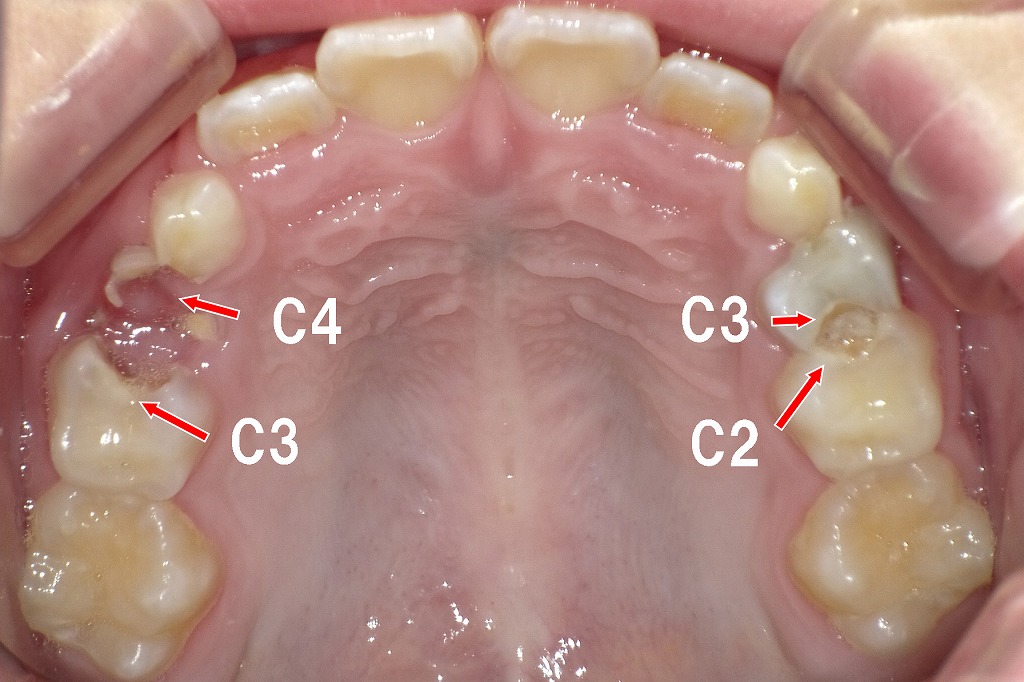

【上の歯の写真:乳歯にC2〜C4の虫歯が多発】

🔍 写真のポイント

- C2(エナメル質を超えて象牙質まで進行)

歯の表面にとどまらず、内側の象牙質まで広がり始めている虫歯です。

画像右側の白濁部や茶色い穴がC2です。 - C3(神経の近くまで到達)

赤い矢印で示されているように、大きく削れた部分が見えます。

象牙質が大きく失われ、痛みが出やすい状態です。 - C4(歯冠が崩壊:根だけ残る段階)

写真左側奥には、歯がほとんど崩れ落ち、根だけが残っている部分があります。

この状態では細菌が溜まりやすく、膿や腫れの原因になります。